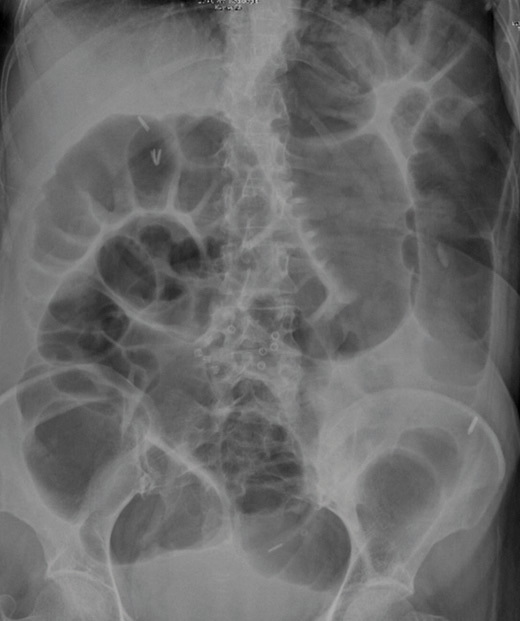

How does small bowel obstruction appear?

>3cm dilation

Dilated loops = coiled spring look